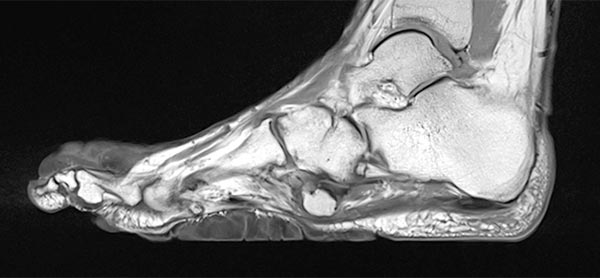

Preoperative imaging of the cerebriform mixed connective tissue nevus in MRI, here sagittal T2-weighted, fat-suppressed sequence of the right foot. The connective tissue nevus is homogeneously hypointense (black) due to the high fibrotic content.

The cerebriform mixed connective tissue nevus is also homogeneously hypointense (black) on sagittal non-enhanced, T1-weighted MRI (same plane).

Sagittal , T1-weighted, fat-suppressed MRI (again, the same plane) shows slight, relatively homogeneous contrast enhancement of the nevus.